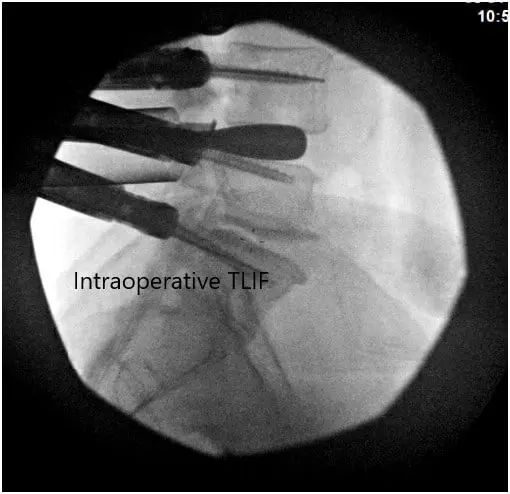

Intraoperative Fluoroscopic Images

Intraoperative Fluoroscopic Images 2

Intraoperative Fluoroscopic Images.